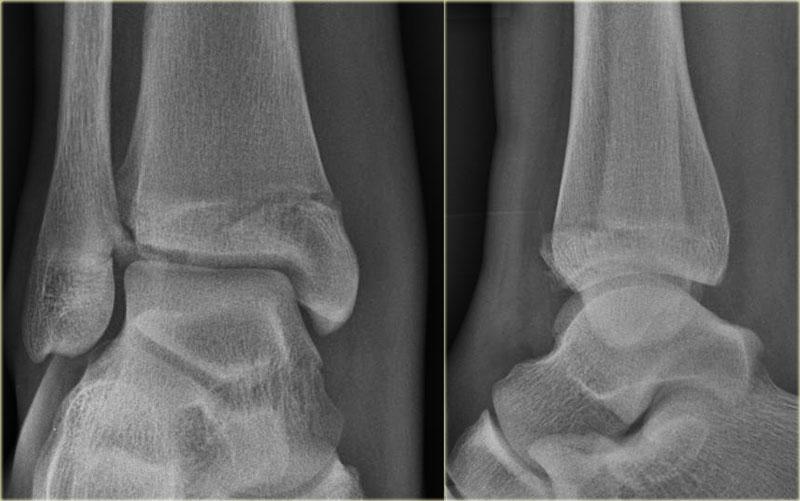

Đây là hình ảnh của một ca bệnh cực kỳ khó.

Bệnh nhân nữ bị bong gân cổ chân và đau cả hai bên trong và ngoài.

Bệnh nhân được bác sĩ đa khoa chuyển đến khoa Chẩn đoán Hình ảnh.

Kỹ thuật viên chụp các tư thế chuẩn gồm thẳng (AP), Mortise và nghiêng, sau đó trình bày cho bác sĩ X-quang, người đã khá băn khoăn khi đọc phim.

Hãy đọc hình ảnh trước, sau đó tiếp tục đọc phần giải thích.

Các dấu hiệu bao gồm:

-

Phù nề phần mềm cả hai bên trong và ngoài (mũi tên đỏ).

Đặc biệt, phù nề phía trong nên gợi ý khả năng chấn thương xoay ngoài – sấp (Weber C). - Đường thấu quang trên tư thế Mortise (mũi tên đen) và tư thế nghiêng. Dấu hiệu này nên gợi ý gãy tertius.

Bác sĩ X-quang quyết định chỉ định CT trước để xác định xem có thực sự có gãy tertius hay không.

Tiếp tục xem hình ảnh CT và bạn sẽ ngạc nhiên.

Hãy cuộn qua các lát cắt.

Thật đáng ngạc nhiên khi một mảnh tertius lớn như vậy lại rất khó nhìn thấy trên phim X-quang.

Cũng lưu ý phù nề phần mềm phía trong gợi ý đứt dây chằng bên trong (mũi tên).

Bạn có thể đoán được đây là loại chấn thương gì không?

Phù nề phần mềm phía trong và gãy tertius đều là dấu hiệu của chấn thương Weber C hoặc chấn thương xoay ngoài – sấp.

Do không thấy gãy xương mác trên phim X-quang cổ chân, phải có gãy xương mác cao.

Khi khám lâm sàng, có phù nề nhẹ phía trong và mặc dù bệnh nhân không than đau ở vùng cao hơn của cẳng chân, vẫn có điểm đau khi ấn vào xương mác.

Vị trí này được đánh dấu và phát hiện đường gãy.

Ca bệnh này minh họa tầm quan trọng của phù nề phần mềm phía trong cũng như dấu hiệu gãy tertius.

Theo phân loại Lauge Hansen, chúng ta có thể kết luận rằng bệnh nhân này đầu tiên bị đứt dây chằng bên trong (giai đoạn 1), tiếp theo là đứt dây chằng chày mác trước (giai đoạn 2), gãy xương mác cao (giai đoạn 3) và cuối cùng là bong mắt cá sau, tức là chấn thương xoay ngoài – sấp (PE) giai đoạn 4.

Trong phẫu thuật, cổ chân được xác định là không vững và vít cố định khớp chày mác đã được đặt vào.

Có chỉ định cố định gãy mắt cá sau vì mảnh gãy chiếm hơn 25% diện khớp của đầu dưới xương chày.